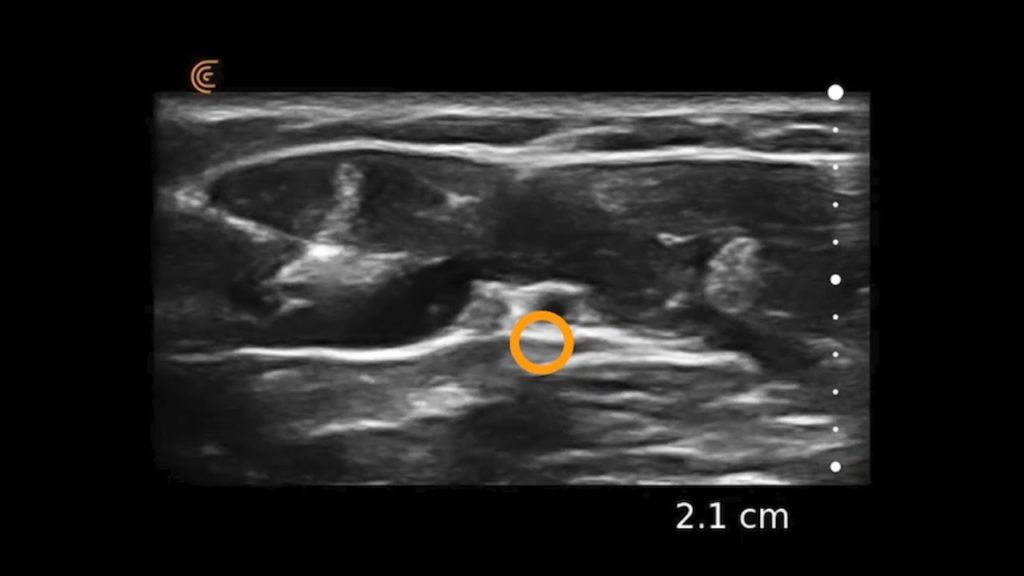

Using the jejunum as an important landmark, the hypoechoic jejunal lymph nodes can be identified. In this video Dr. Edwards explains the ultrasound appearance of normal jejunal nodes.